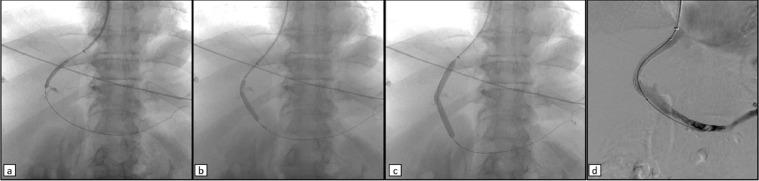

Duodenal varices are ectopic varices that can cause severe and life-threatening gastrointestinal bleeding. Diagnosis and treatment of ectopic varices is challenging, because endoscopy is often unproductive in detecting and treating ectopic varices. Interventional radiology appears as an alternative in this setting, thanks to its important role in treating the bleeding caused by ectopic varices and in preventing rebleedings. We present an interesting case of bleeding ectopic varices in a male 62-years-old cirrhotic patient (Child-Pugh B8). The patient presented with hemorrhagic shock caused by massive melena. CT angiography showed intraluminal blood and identified the source of bleeding as an ectopic varicose vein draining into the superior mesenteric vein. Interventional radiology approach was the only applicable one to reach and effectively treat the source and cause of bleeding by TIPS placement and embolization of the collateral feeding at the same session.

十二指肠静脉曲张是一种异位静脉曲张,可导致严重且危及生命的胃肠道出血。异位静脉曲张的诊断和治疗具有挑战性,因为内镜检查在检测和治疗异位静脉曲张方面往往效果不佳。在这种情况下,介入放射学似乎是一种替代方法,这得益于其在治疗异位静脉曲张引起的出血以及预防再出血方面的重要作用。我们报告了一例有趣的病例,一名62岁的男性肝硬化患者(Child-Pugh B8级)出现出血性异位静脉曲张。患者因大量黑便导致失血性休克。CT血管造影显示管腔内有血液,并确定出血源为一条汇入肠系膜上静脉的异位曲张静脉。介入放射学方法是唯一适用的方法,可通过在同一次手术中放置经颈静脉肝内门体分流术(TIPS)和栓塞侧支供血来有效到达并治疗出血源及病因。